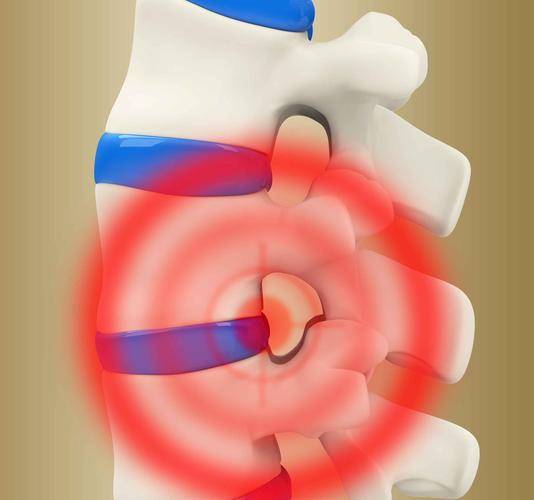

3、脊髓壓迫

隨著肺部癌細胞的不斷增長、擴散,其很可能會對脊髓、脊神經以及向脊髓供應血液的血管造成壓迫,若脊髓壓迫未得到及時有效的治療,則很可能會因神經損傷而導致出現永久性殘疾。

脊髓壓迫的症狀一般為手指或腳趾麻木、大小便失禁或是走路困難。